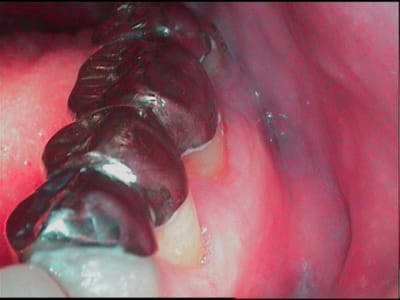

Voilà, je vous présente un nouveau patient, j'aurais aimé avoir votre avis sur les possibilités de traitement.....j'ai déjà réaisé une gouttiere de relaxation maxillaire.

Les 4 incisives mandibulaires, sont nécrosées.

merci pour vos conseils.....en gros c un cas de bridge complet haut et bas (un fois qu'on aura une bonne détente neuro musculaire) en passant par une phase de provisoires pour tester la dv....mais comment savoir qu'elle sera la bonne dv et si le patient la suportera...???

je crois que le cas de Jay est plus complexe, et compliqué aussi par des mylolyses (visibles faces vest des incisives) et dont l'évolution, meme apres correction de l'occl, pourrait nuire a la retention ( sur les dents qu'il garderait vivantes)